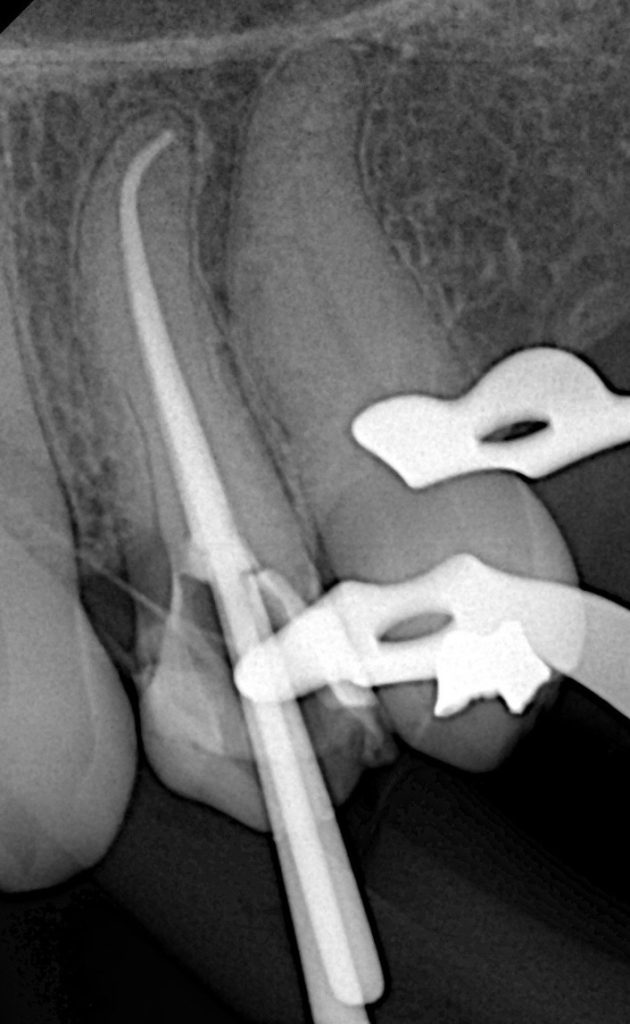

This case demonstrates the complete management of a maxillary premolar with irreversible pulpitis and compromised coronal structure. The treatment involved root canal therapy under rubber dam isolation, followed by adhesive restoration to ensure functional and esthetic rehabilitation.

4. Cleaning & Shaping